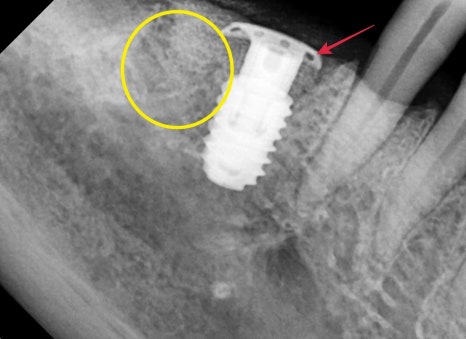

초진 사진입니다.

빨간색 원으로 표시된 부분이 특히 뼈가 많이 녹아 많이 흔들렸으며

나머지 치아들도 전반적으로 동요도가 있었습니다.

심한 치주 질환으로 인해 흡수된 공간 임플란트 수술

오른쪽 아래 임플란트 수술 시 뼈의 상태입니다.

일반적으로 심한 치주염의 경우 염증이 바깥쪽 뼈를 녹여

임플란트를 식립하더라도 뼈안에 심기가 어렵고

임플란트가 일부 노출이 될 수밖에 없습니다.

사진상으로 봐도 아래의 뚜껑부위는 지붕처럼 추가적인 구조가 추가되어 있고

모양이 다른것들과 조금 다릅니다